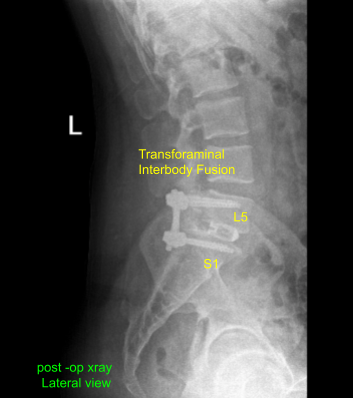

Postoperative X Ray showed there is a normal lumbar lordosis. There were no destructive abnormalities or fractures. The intervertebral disc spaces appear preserved. There was no spondylolisthesis. The facet joints appear unremarkable.

The patient followed up in our office two weeks after the surgery, with their post operative images. During this visit we discussed home exercise programs for rehabilitation of the back. We went over the X Rays and the surgical procedure. They agreed to continue icing to keep the swelling to a minimum and to continue to utilizing early mobilization and mechanical prophylaxis to reduce the chances of a deep vein thrombosis.